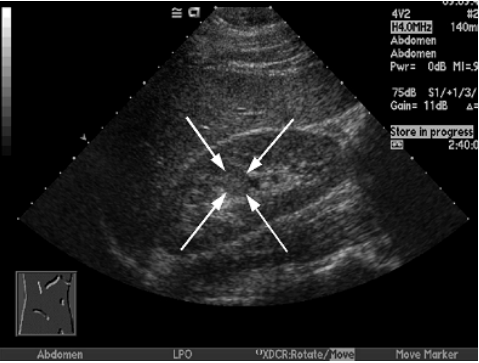

68.附圖中箭號所指的構造最可能為:

(A)腎腫瘤 (B)腎囊腫 (C)腎柱(renal column) (D)擴張之腎盞(dilated calyces)